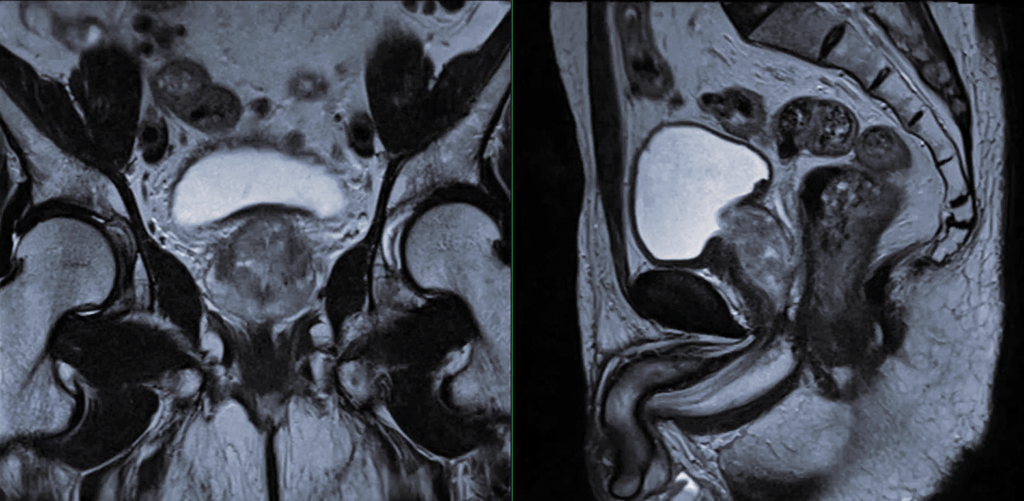

Prostate Cancer Awareness

Prostate cancer causes over 3000 deaths in Australian men each year. This makes prostate cancer the fourth main cause of death in Australian males. The risk of prostate cancer increases with age and family history. By the age of 85, approximately 1 in 6 Australian males will be diagnosed with prostate cancer.